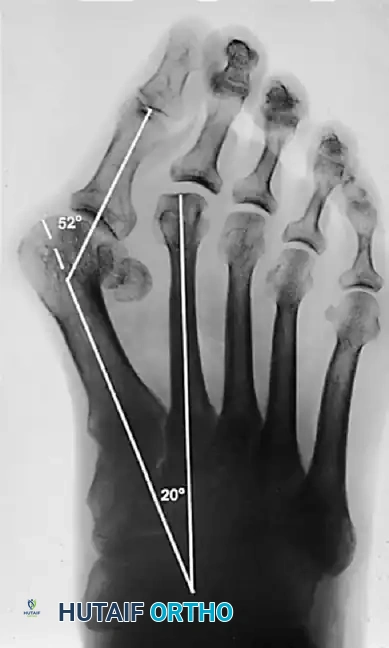

Standard weight-bearing anteroposterior (AP), lateral, and sesamoid axial radiographs are mandatory. Surgical decision-making relies heavily on precise angular measurements.

Key Radiographic Parameters

• Hallux Valgus Angle (HVA): The angle between the longitudinal axes of the first metatarsal and proximal phalanx. Normal is < 15°.

• Intermetatarsal Angle (IMA): The angle between the longitudinal axes of the first and second metatarsals. Normal is < 9°.

• Distal Metatarsal Articular Angle (DMAA): The angle between the articular surface of the first metatarsal head and the longitudinal axis of the metatarsal shaft. Normal is < 10°. An increased DMAA indicates a congruous joint in a valgus position, necessitating a specific intra-articular or extra-articular corrective osteotomy.

Surgical Warning: Failure to recognize an abnormal DMAA will lead to undercorrection or early recurrence. If a standard proximal osteotomy is performed without addressing the valgus articular orientation, the joint will remain congruous in valgus, and the deformity will persist.

Surgical Decision Making: The Algorithm

With over 130 operations described for hallux valgus, procedure selection must be tailored to the severity of the deformity, the presence of arthritis, and the stability of the first TMT joint.

1. Mild Deformity (HVA < 30°, IMA < 13°): Distal metatarsal osteotomy (e.g., Chevron) with lateral soft tissue release.

2. Moderate Deformity (HVA 30°–40°, IMA 13°–20°): Diaphyseal osteotomy (e.g., Scarf) or proximal metatarsal osteotomy (e.g., Ludloff, Crescentic) combined with a distal soft tissue procedure.

3. Severe Deformity (HVA > 40°, IMA > 20°): Proximal metatarsal osteotomy or First TMT joint arthrodesis (Lapidus procedure), especially if hypermobility is present.